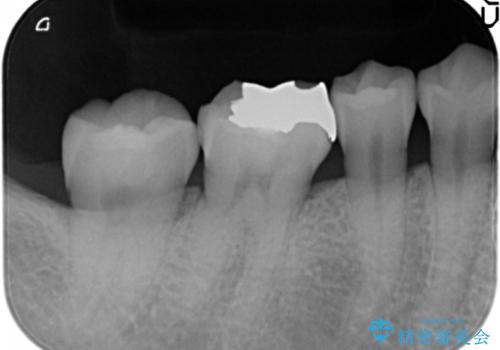

銀歯を白く セラミックインレーに

- 銀歯にしたのが20年以上前とのことで、白くやりかえたいということでした。

セラミックインレーにしています。

- 7万円(左下6 emaxプレスインレー 7万円)費用は治療当時の料金となります

銀歯を外して、下に虫歯があればしっかり取ります。しみるなどの症状が出る前がおすすめです。